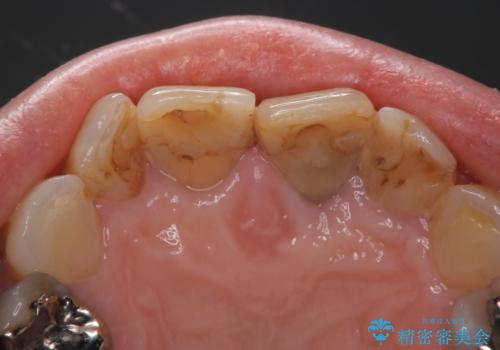

- 前歯の着色が気になるということを主訴に来院された患者様です。

以前に、根管治療をされているみたいなのですが、そのまま放置されていてどんどん着色がひどくなり来院されました。

神経の治療をしている歯は、時間と共に色がどんどん変色していきます。

また、神経、血液供給がなくなってしまうので歯も脆くなっていってしまう為、歯が割れてしまうリスクもあります。

- 天然歯を削ります